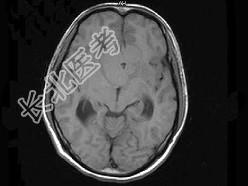

- 单项选择题男,32岁, 头痛,头昏半年, 加重10天伴抽搐,根据所提供图像, 最可能的诊断是 ( )

A、胶质瘤

B、颅咽管瘤

C、蛛网膜囊肿

D、表皮样囊肿

E、胆脂瘤